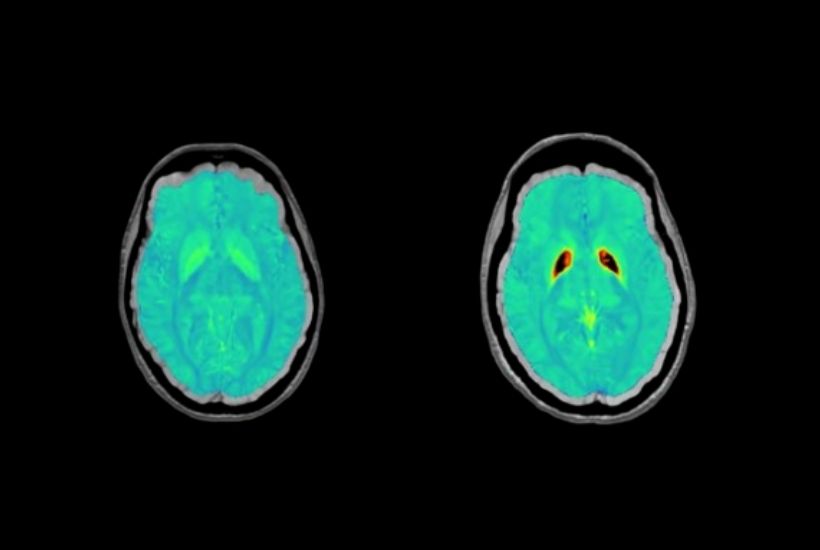

CHU Bordeaux

MALADIE RARE : NBIA

Objectifs et résultats

Identifier les régions impactées au niveau de la subtance grise profonde :

- cinétique de l’accumulation de fer, profil d’évolution de la maladie dans le temps

- facteurs génétiques

- lien avec le développement neurocognitif dès l’enfance

- ouvrir la voie au développement de thérapies